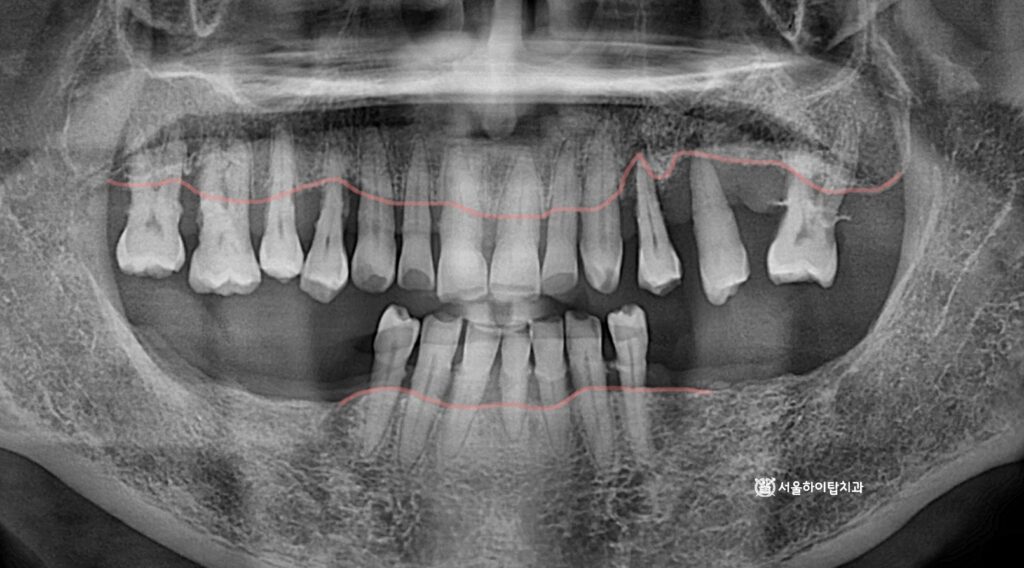

초진 파노라마 엑스레이입니다.

주안동 치과 에서는 전체적으로

뼈의 높이가 낮아진 것을

한눈에 확인할 수 있습니다.

특히 아래턱 양쪽 구치부는

이미 어금니가 모두 상실되었으며,

위턱은 사진 기준 오른쪽 구치부에

심한 염증이 관찰됩니다.

이로 인해 치아들이 마치 공중에 떠 있는 듯한

‘Floating Tooth’ 모습으로 나타나고 있습니다.

즉, 일부 자연치는

주변 뼈 지지가 거의 없기 때문에

장기적인 유지가 어려운 상태,

즉 Hopeless Tooth 임을 시사합니다.